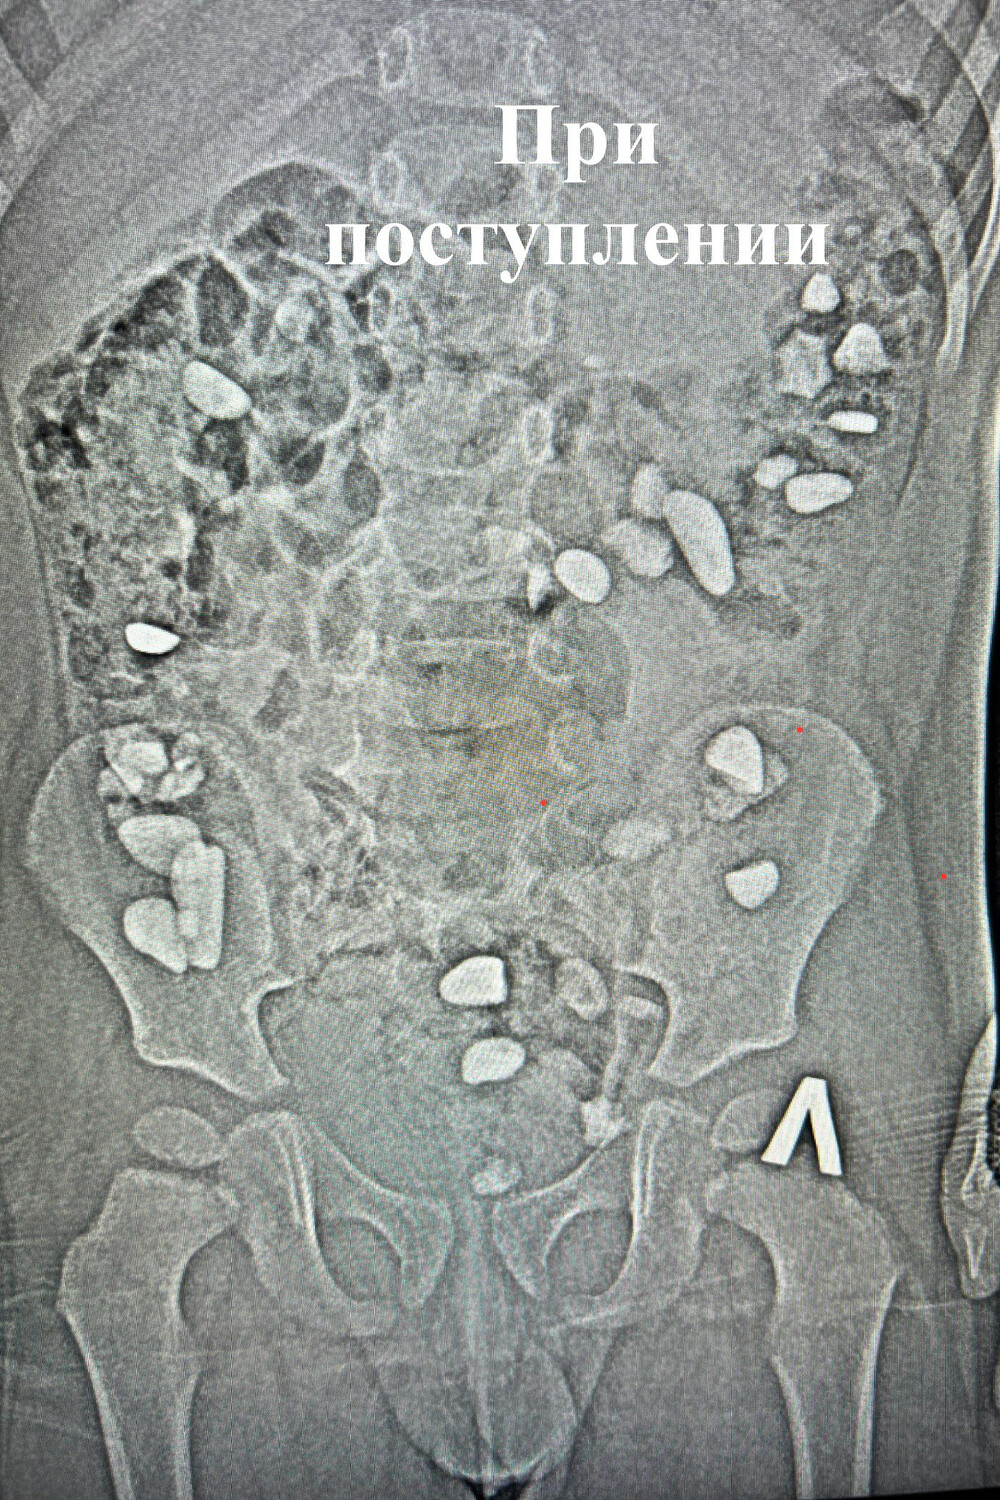

Недавно в Ессентукскую городскую клиническую больницу поступил ребенок, который проглотил более 25 камней. Это выяснилось во время рентгенологического исследования, и его родители не знали, при каких обстоятельствах все произошло.